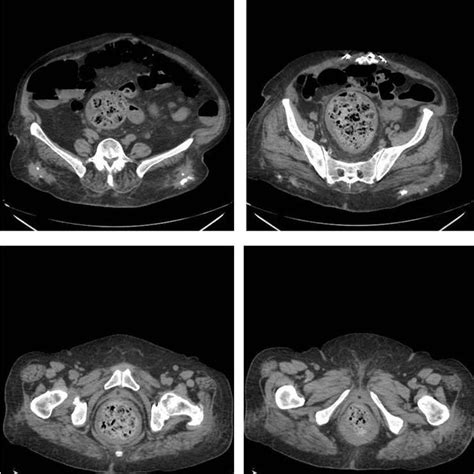

Los fecalomas se definen como una masa de heces acumuladas, sobre todo a nivel del colon distal y del recto, con una presentación clínica muy diversa que puede incluir masas abdominales, retención urinaria o megacolon tóxico. Suelen producirse en el sigma y en el recto por la disminución progresiva del calibre y el fenómeno de la coprostasis, siendo más frecuentes en pacientes ancianos, con estreñimiento crónico o lesiones medulares.

Desde el punto de vista clínico, los fecalomas pueden pasar desapercibidos inicialmente debido a la presencia de diarrea por rebosamiento. También pueden manifestarse como masas abdominales que condicionan síntomas por compresión de estructuras vecinas, con clínica incluso extradigestiva como puede ser la incontinencia urinaria. En casos más avanzados llegan a producir megacolon tóxico o retención urinaria. Las complicaciones más severas son la insuficiencia respiratoria, la perforación intestinal o la uropatía obstructiva. La presentación en forma de obstrucción intestinal con dolor y distensión abdominal, náuseas y vómitos es rara.